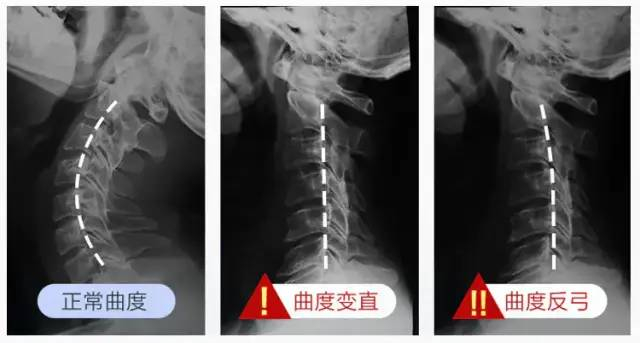

长期保持不健康的习惯,颈椎就会变直,严重的甚至会出现反弓,直接压迫颈部,很难受。